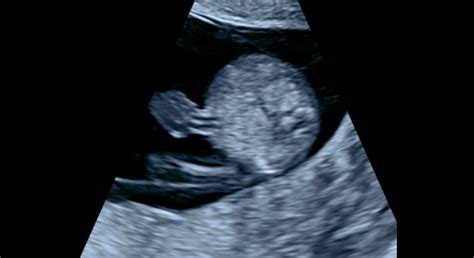

Prvý ultrazvuk v tehotenstve je ideálne robiť medzi 8. až 10. týždňom tehotenstva, kedy je aj najvhodnejší čas na ultrazvukové datovanie dĺžky gravidity podľa CRL (Crown-Rump-Length - temeno-kostrčová vzdialenosť). Tento ultrazvuk verifikuje, či je tehotenstvo v maternici, či je plod vitálny (má akciu srdiečka) a či nie je viacpočetné. Vďaka ultrazvuku môžete počuť aj tlkot srdiečka vášho bábätka.

- Ultrazvukové vyšetrenie: Počas tehotenstva ho absolvujete viackrát. Okrem prvého trimestra, kedy slúži na potvrdenie tehotenstva a datovanie, sa vykonáva aj v 18. až 23. týždni a po 30. týždni tehotenstva. K dispozícii je klasický 2D, ako aj 3D a 4D ultrazvuk. 3D fotografie a videá bábätka sú nadštandardom, ktorý zdravotné poisťovne nepreplácajú.

Špeciálnym tehotenským vyšetrením je ultrazvuk. Počas tehotenstva ho absolvujete viackrát, a to koncom prvého trimestra (najčastejšie od 11. do 14. týždňa tehotenstva), v 18. až 23. týždni tehotenstva a po 30. týždni tehotenstva. Veľké množstvo výskumov a štúdií nedokázalo škodlivý vplyv ultrazvukového vyšetrenia na plod a tehotnú ženu.